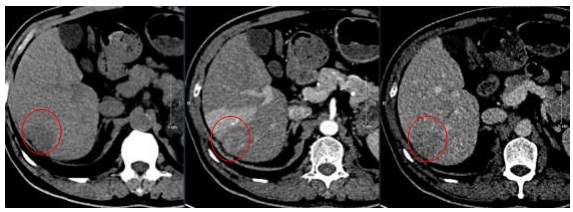

– Đánh giá về hình ảnh:

Hình 5: Hình ảnh CT ổ bụng trước điều trị (11/2019): U gan hạ phân thuỳ VI, kích thước 2,5×3,5cm, ngấm thuốc tính chất HCC (vòng tròn đỏ)

Nhận xét: Trước điều trị khối u ngấm thuốc điển hình của HCC (hình 5), tuy nhiên sau điều trị ở thời điểm 9 tháng trở đi khối u giảm về kích thước, không ngấm thuốc sau tiêm nên đạt được bệnh đáp ứng hoàn toàn theo tiêu chuẩn mRECIST (hình 6,7,8,9).